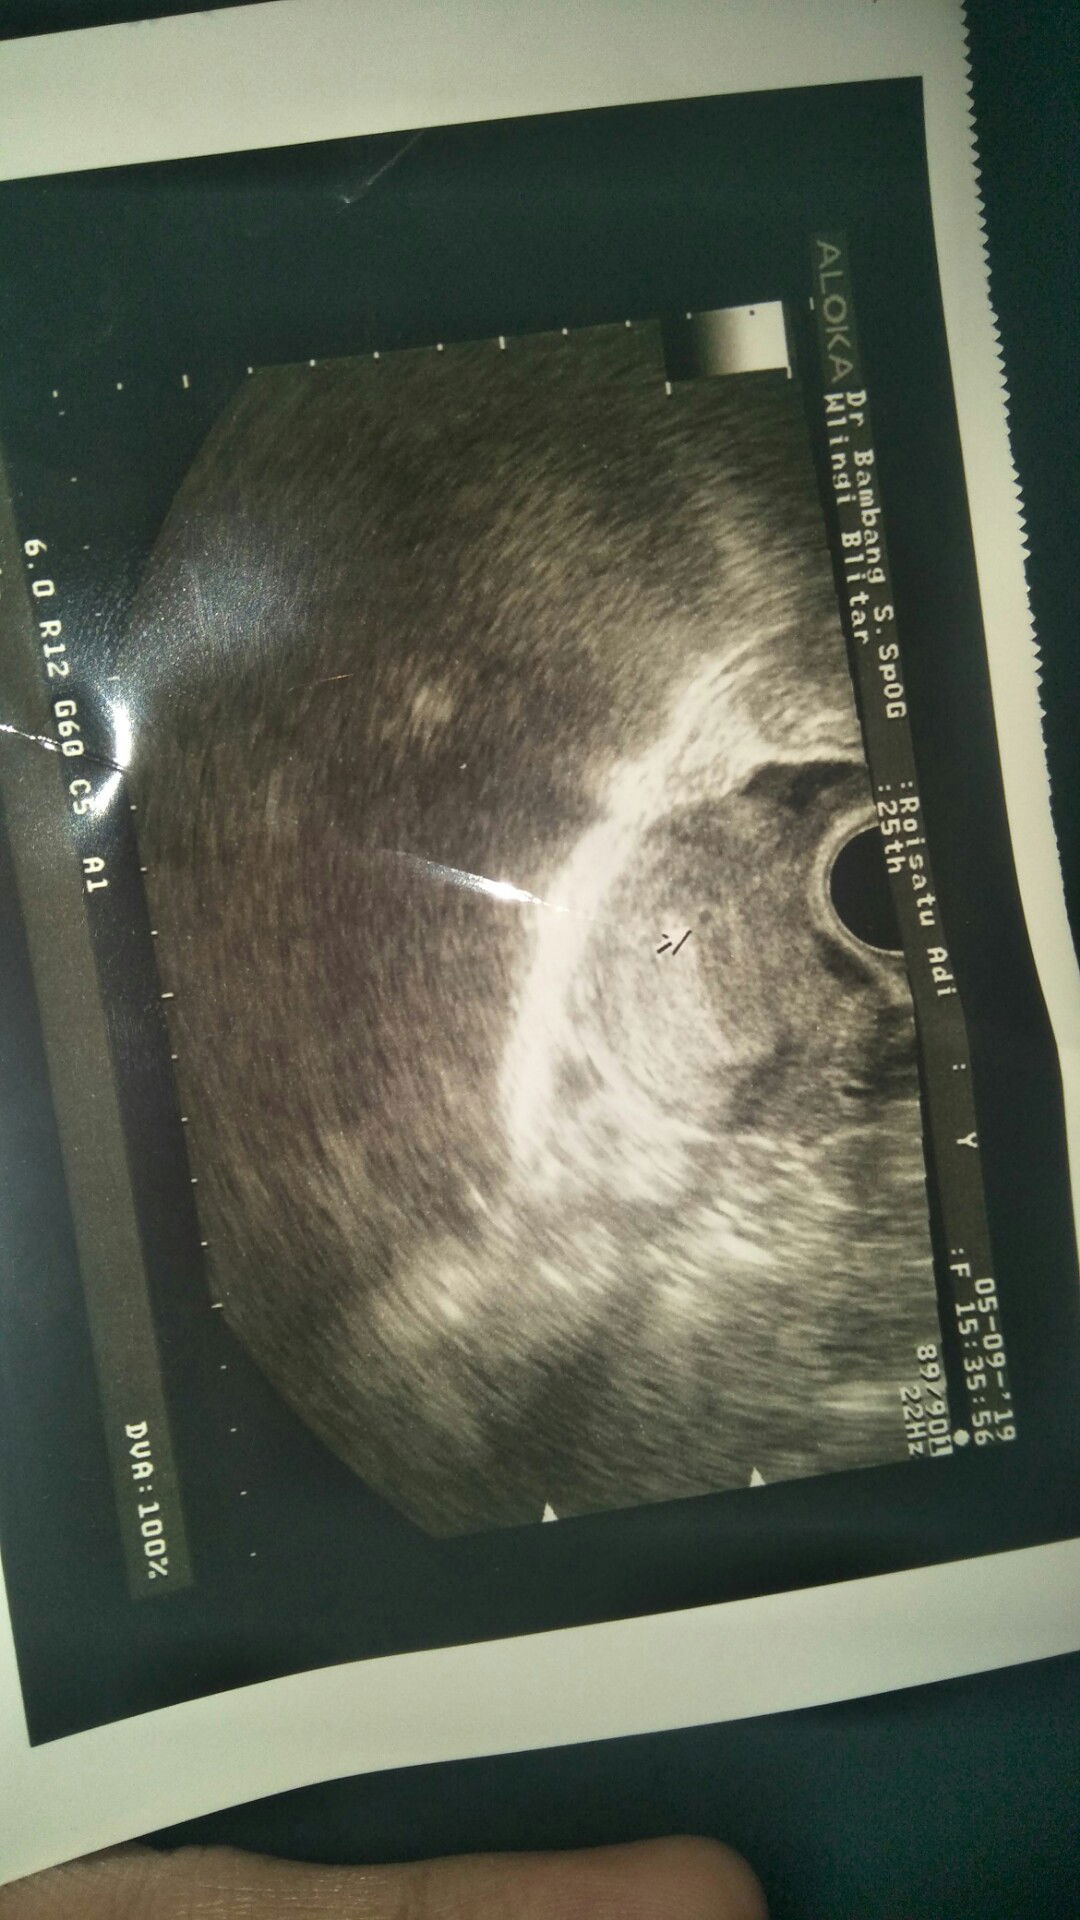

Bunda bunda ada yg pernah merasakan kram perut dan kencang pada kehamilan yang masih usia sekitar 5 minggu ? Ini hasil usgnya masih keliatan satu titik aja bunda bunda kantongnya, tapi perut rasanya sering kram dan kencang gitu